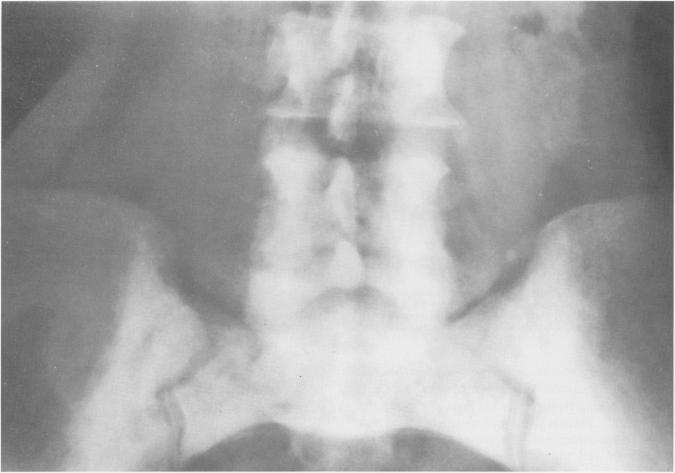

Mastocytosis is a rare disease of mast-cell proliferation with involvement of the reticuloendothelial systems including skin, bone, gastrointestinal tract, liver, lungs, spleen, and lymph nodes. Systemic mastocytosis is characterized by a combination of symptoms that relate to the mast cells' release of vasoactive substances, such as histamine. These symptoms include urticaria pigmentosa, flushing, syncope with hypotension, headaches, nausea, vomiting, diarrhea, and occasional bronchospasm. The diagnosis of mastocytosis is typically based on the presence of the characteristic extraosseus manifestations. A well recognized roentgenographic feature seen in 70-75% of patients with mastocytosis is diffuse osteolysis and osteosclerosis, affecting primarily the axial skeleton and the ends of the long bones. Rarely, the bony involvement consists of generalized osteoporosis, which may lead to pathologic fracture, or solitary lesions (mastocytomas) which may cause symptoms of localized pain. Four patients with previously diagnosed systemic mastocytosis had unusual skeletal lesions. Clinical and laboratory evaluation of these patients eventually led to the correct diagnosis of systemic mastocytosis. We report these four cases to emphasize the need for thorough evaluation of unusual musculoskeletal findings in association with extraosseus symptoms that are characteristic of mastocytosis. Knowledge of a wide differential diagnosis of unusual skeletal lesions should include systemic mastosytosis.

肥大细胞增多症是一种罕见的肥大细胞增殖性疾病,累及包括皮肤、骨骼、胃肠道、肝脏、肺、脾脏和淋巴结在内的网状内皮系统。系统性肥大细胞增多症的特征是一系列与肥大细胞释放血管活性物质(如组胺)相关的症状。这些症状包括色素性荨麻疹、潮红、伴有低血压的晕厥、头痛、恶心、呕吐、腹泻以及偶尔的支气管痉挛。肥大细胞增多症的诊断通常基于特征性的骨外表现。在70% - 75%的肥大细胞增多症患者中可见一种公认的X线特征,即弥漫性骨质溶解和骨质硬化,主要影响中轴骨骼和长骨末端。极少情况下,骨骼受累表现为全身性骨质疏松,可导致病理性骨折,或孤立性病变(肥大细胞瘤),可引起局部疼痛症状。4例先前诊断为系统性肥大细胞增多症的患者有不寻常的骨骼病变。对这些患者的临床和实验室评估最终得出了系统性肥大细胞增多症的正确诊断。我们报告这4例病例,以强调对于伴有肥大细胞增多症特征性骨外症状的不寻常肌肉骨骼表现进行全面评估的必要性。对不寻常骨骼病变进行广泛鉴别诊断的知识应包括系统性肥大细胞增多症。